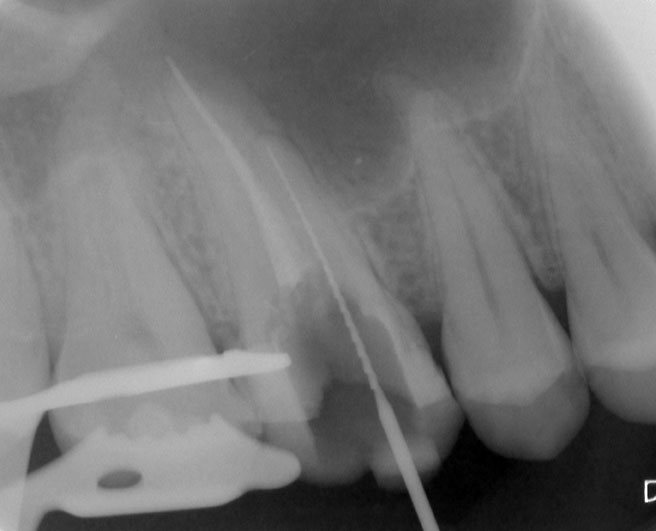

Nach Darstellung aller Wurzelkanaleingänge wird in einem zweiten Schritt das frakturierte Wurzelkanalinstrument dargestellt (Abb. 3 u. 4). Hierfür verwenden wir den Aufsatz 3E des Tigon+. Durch die schmale und lange Form des Instruments erreichen wir einen tiefen und schmalen Zugang.